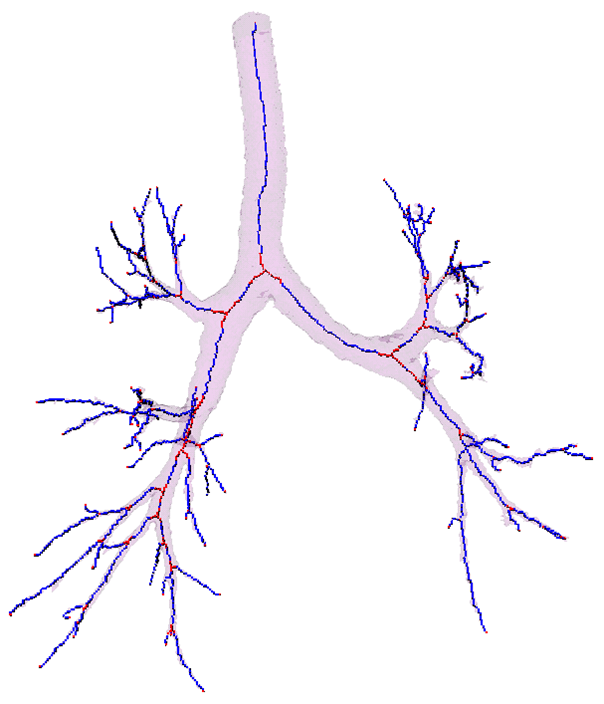

The key steps are now illustrated:

Segmentation - adaptive region growing (left), extracting centerlines - topologically and geometrically correct thinning (middle), and excluding branch-areas based on 3D distance map calculation (right).

Partitioning centerlines in a formal tree data structure (left), partitioning segmented tree via isotropic label propagation (middle), and quantitative analysis formal XML tree with associated measurements (right).